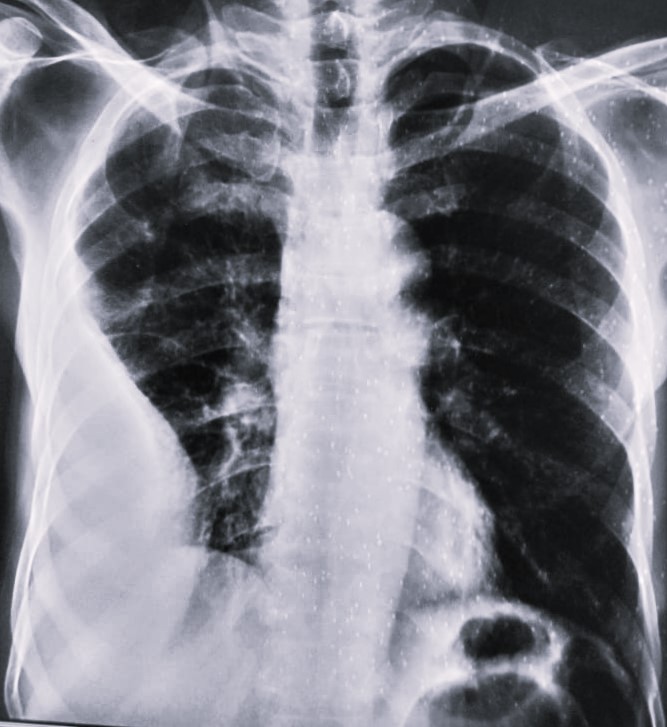

| 333 | IGGMC, Nagpur, Nagpur | P2 | 29-4139 | Nikita Wasnik | Consent taken on Paper | 28 Yrs. |

Provisional Diag : Bronchiectasis

Final Diag : Primigravida Acute Bronchiectasis With Type 2 Infection |

Result awaited (Suspected TB/Non-TB) | Abnormality visible on x-ray |